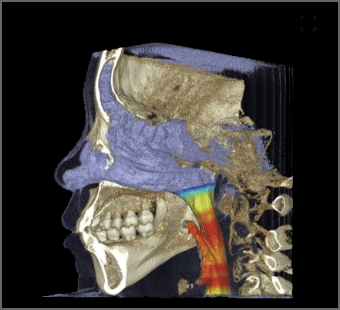

舌、気道など軟組織の評価にも活用されています。

- 0.3秒の撮影で瞬間キャプチャー

- 瞬間キャプチャで認識できない微細な動きによる画像エラーまで最小化

- 髪の毛も写る好感度の画像

- 髪の毛は線量が高いと透過されて画像上では写らない。高感度・低線量で安心撮影

- 矯正専門分析用の画像

- 誤差を許さいない矯正分析に必要な臨床ポイントが明確に撮影、オートトレーシングまで対応

- ノーズラインも明瞭に表現